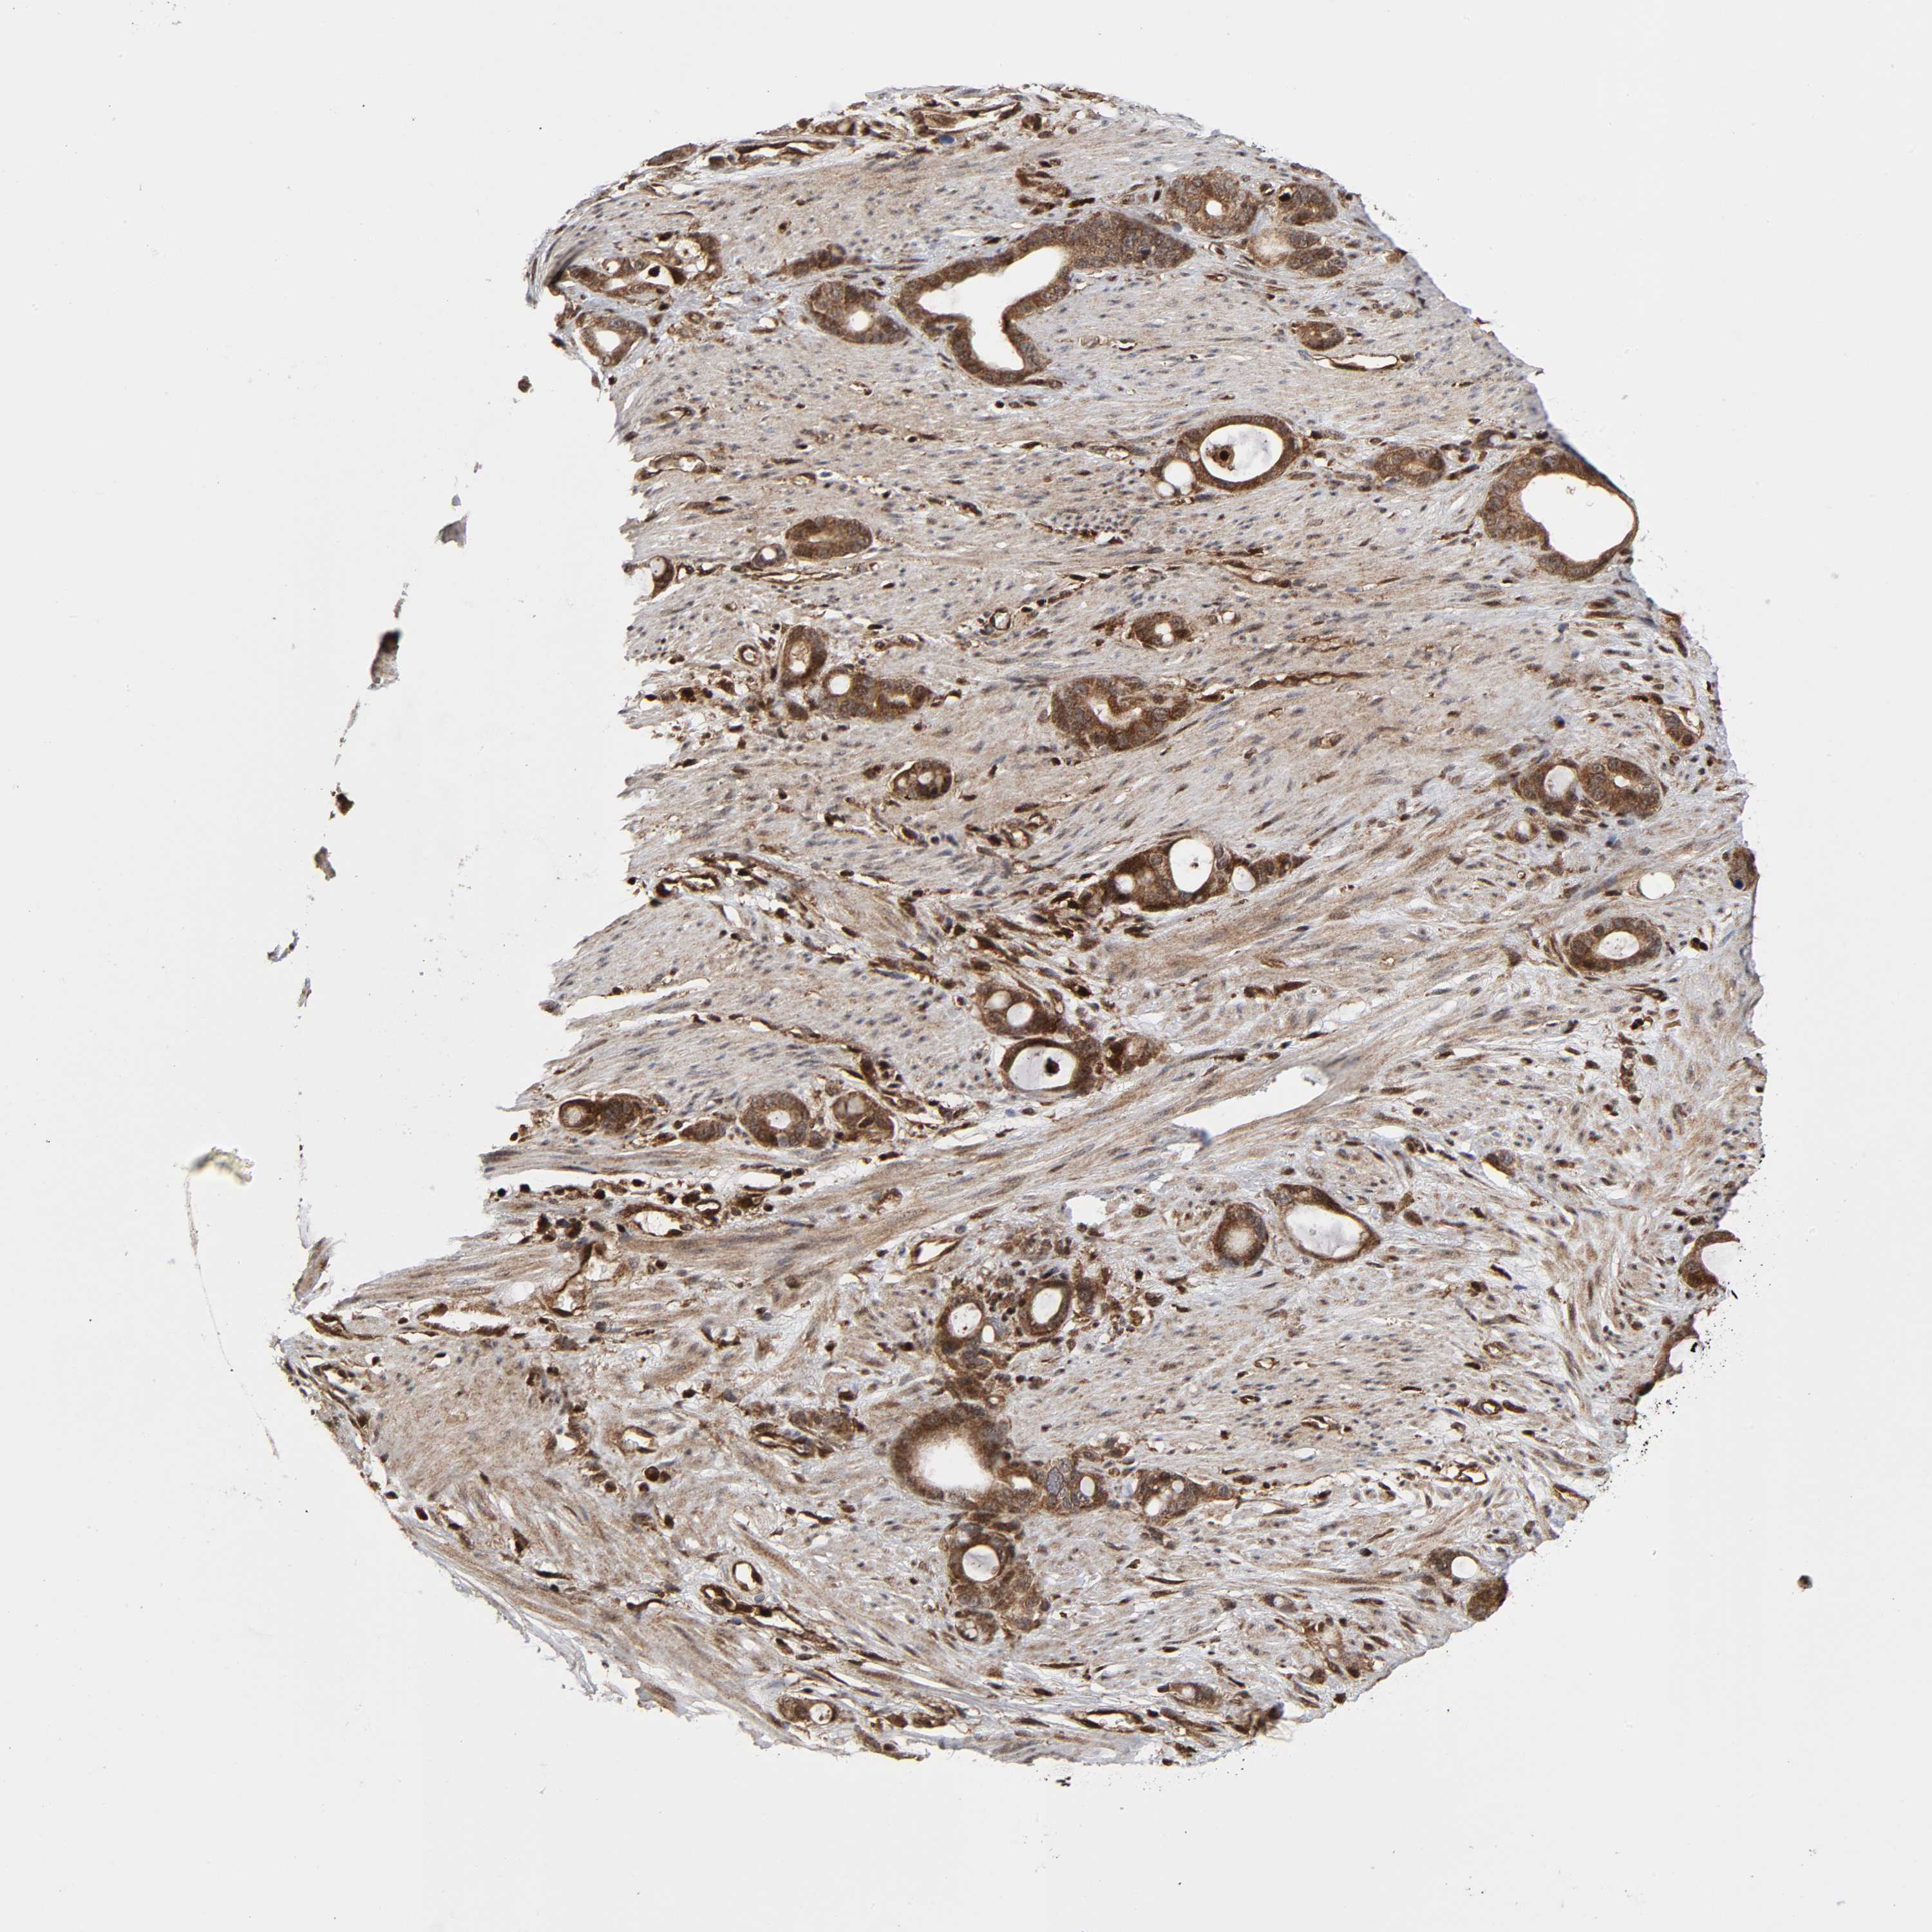

STOMACH CANCER - Protein expressioni

A mouse-over function shows sample information and annotation data. Click on an image to view it in a full screen mode. Samples can be filtered based on level of antibody staining by selecting one or several of the following categories: high, medium, low and not detected. The assay and annotation is described here.

Note that samples used for immunohistochemistry by the Human Protein Atlas do not correspond to samples in the TCGA dataset.

Antibody stainingi

Antibody staining in the annotated cell types in the current human tissue is reported as not detected, low, medium, or high, based on conventional immunohistochemistry profiling in selected tissues. This score is based on the combination of the staining intensity and fraction of stained cells.

Each image is clickable and will lead to virtual microscopy that enables deeper exploration of all samples and also displays staining intensity scores, fraction scores and subcellular localization as well as patient and tissue information for each sample.

Adenocarcinoma, NOS

Adenocarcinoma, High grade